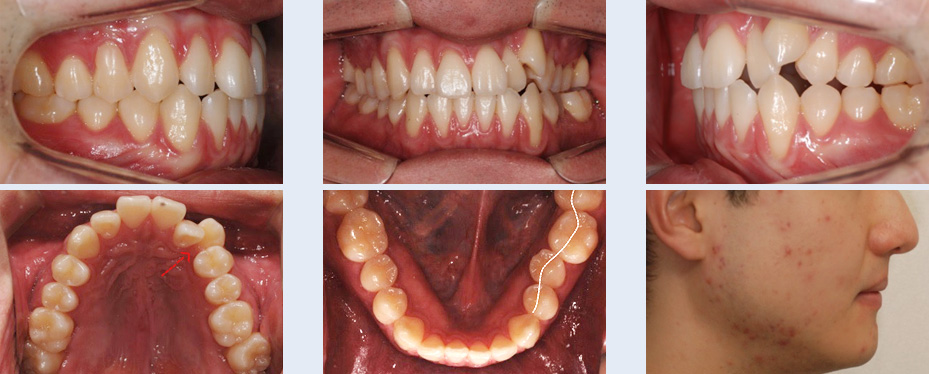

앞니 치열 불규칙하고 어금니가 잘 맞물리지 않아 소리가 나는 증상으로 내원한 22세 대학생입니다.

좌측 위 덧니가 관찰되었고 아래 어금니 배열이 바르지 않아 위 어금니와 정상적인 교합 관계를 보이지 않는

상태였습니다. 이를 빼지 않고 공간을 확보하기 위해 다음의 치료를 진행하였습니다.

앞니 치열이 고르게 개선 되었으며 어금니가 자연스럽게 맞물리는 정상교합이 되었습니다. 자연치아를 빼지 않고

약간의 치간 삭제를 통해 교정 치료가 완료되어 환자 분의 만족도가 높은 케이스였습니다.